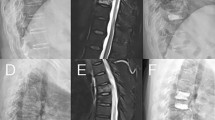

The study included patients with single-segment OVCF who underwent PKP at our medical institution between January 2018 and December 2022. The inclusion criteria were as follows:1 single-segment vertebral fractures caused by low-energy trauma (such as bending, falling, etc.) after PKP, resulting in back pain or restricted mobility;2 X-ray or CT imaging indicating vertebral compression fractures, with MRI confirming recent vertebral fractures;3 complete medical records. The exclusion criteria were:1 fractures involving two or more vertebral segments;2 vertebral fractures due to tumors, infections, or tuberculosis;3 fractures with posterior wall instability or burst fractures;4 severe spinal degeneration;5 spinal cord compression with neurological symptoms;6 poor cardiopulmonary function, unable to tolerate surgery;7 loss to follow-up or incomplete imaging data.

BMD was measured using a dual-energy X-ray absorptiometry scanner. A Cobb angle greater than 10° in the coronal view was defined as scoliosis. On the anteroposterior and lateral X-ray films, bone cement leakage was defined as bone cement exceeding the boundaries of the vertebral body. The distribution of bone cement was assessed by examining whether it crossed the midline and whether it was symmetrical on the postoperative anteroposterior X-ray. Crossing the midline was considered sufficient distribution, whereas not crossing it was deemed insufficient. The formula for calculating the AVHRR was as follows: AVHRR = [2 × (post-op AVH - pre-op AVH) / (upper vertebral body anterior height + lower vertebral body anterior height of the fractured vertebra)] × 100%. The anti-osteoporosis treatment regimen included oral calcium (600 mg/day) and active vitamin D (0.25 µg/dose, twice daily) as basic therapy, combined with zoledronic acid intravenous infusion (5 mg/dose, once a year) or denosumab subcutaneous injection (60 mg/dose, once every six months). Cement distribution pattern: classified into four categories:1 contact only with the upper vertebral endplate2, contact only with the lower vertebral endplate3, contact with both the upper and lower vertebral endplates, and4 contact with neither the upper nor the lower vertebral endplates (Fig. 1).